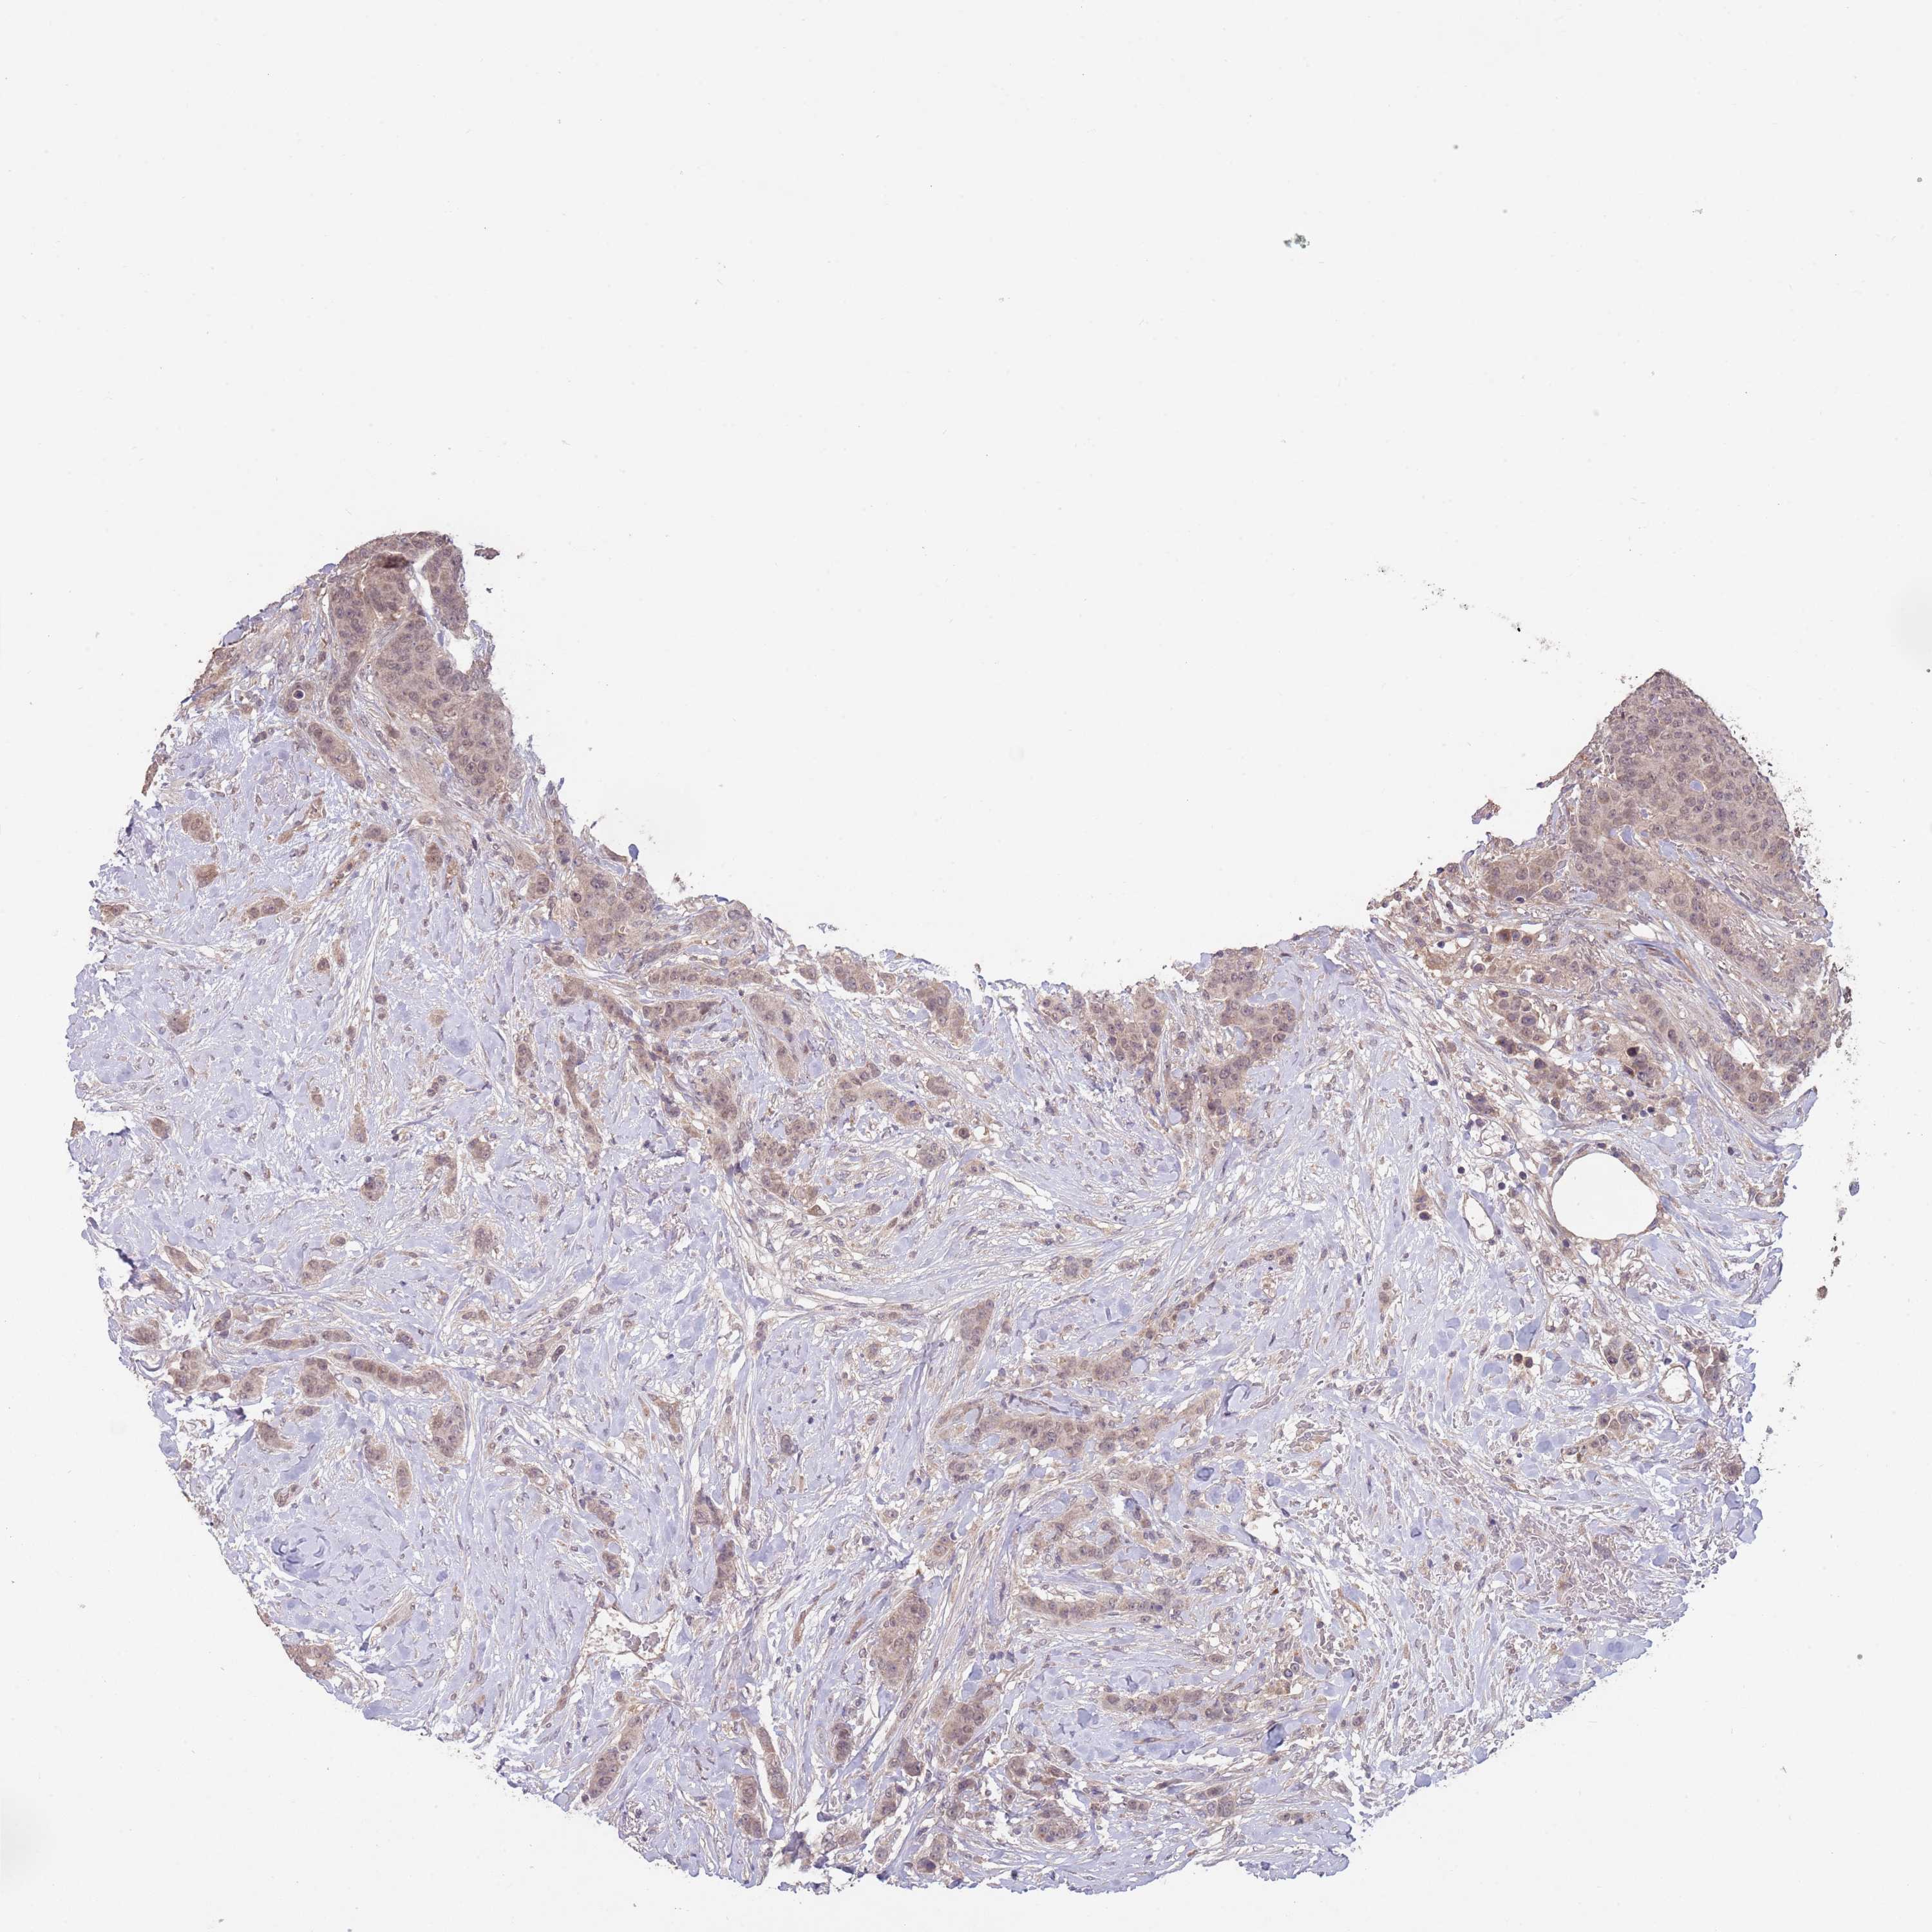

CANCER BREAST CANCER Show tissue menu

BRCA TCGA BRCA VALIDATION PROTEIN EXPRESSION

Breast cancer

Human cancer